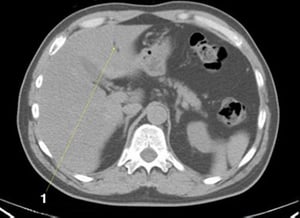

CT-Scan von Abdomen und Becken mit normaler Anatomie ohne Kontrastmittel (Folie 22)

1 = M. iliaca.

© Springer Science+Business Media